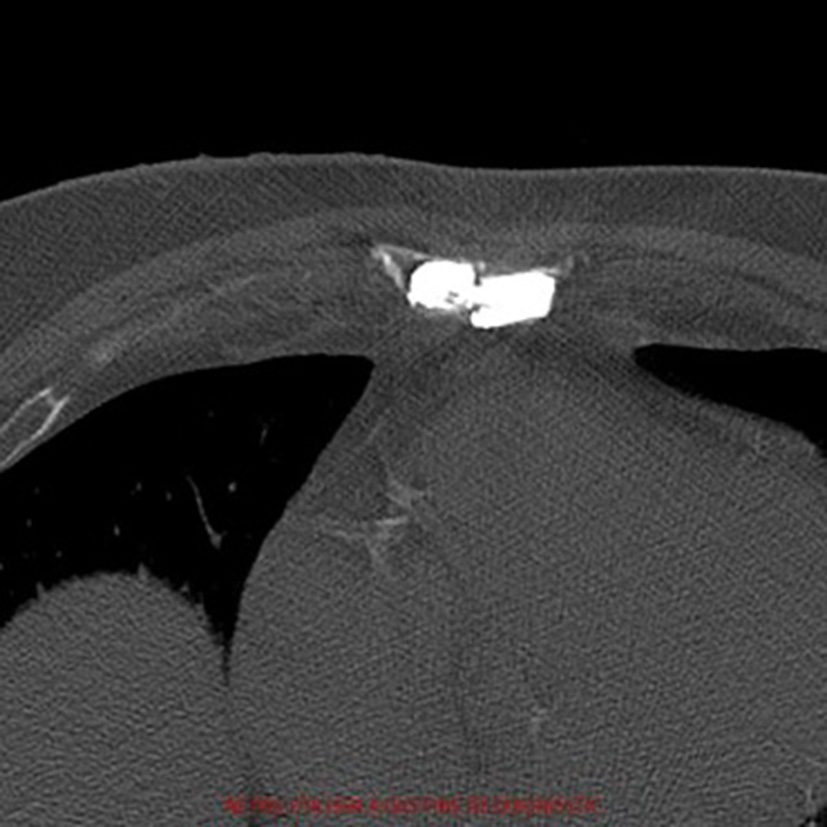

Figure 2

Post-operative axial computed-tomography image of patient 1. The radiopaque cement fills the pseudathrosic parts of the sternum to reduce the pain and a bridge is created for a better stabilization.